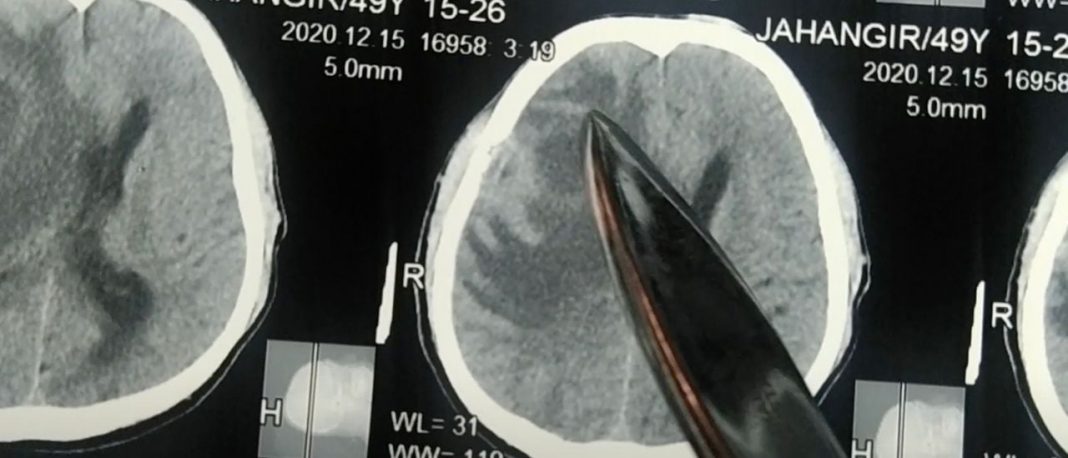

Health officials are investigating a growing number of brain abscesses in children first noticed in Las Vegas but now rising in other parts of the country too.

Dr. Taryn Bragg, an associate professor at the University of Utah and the only pediatric neurosurgeon for the state of Nevada, began noticing a large increase in cases of brain infections among children beginning in March 2022. “I was seeing large numbers of cases and that’s unusual,” Bragg told CNN in a Friday report.

During that time, the number of brain abscesses in kids tripled in Nevada, rising from an average of four to five a year to 18, the outlet reported. As the only doctor treating the cases in the state of Nevada, Bragg took note of this unusual increase and notified public health authorities.

Bragg revealed that cases all began similarly, starting off as a common complaint such as an earache or sinus infection. Within a week, however, it was evident that the children were suffering from something more severe.